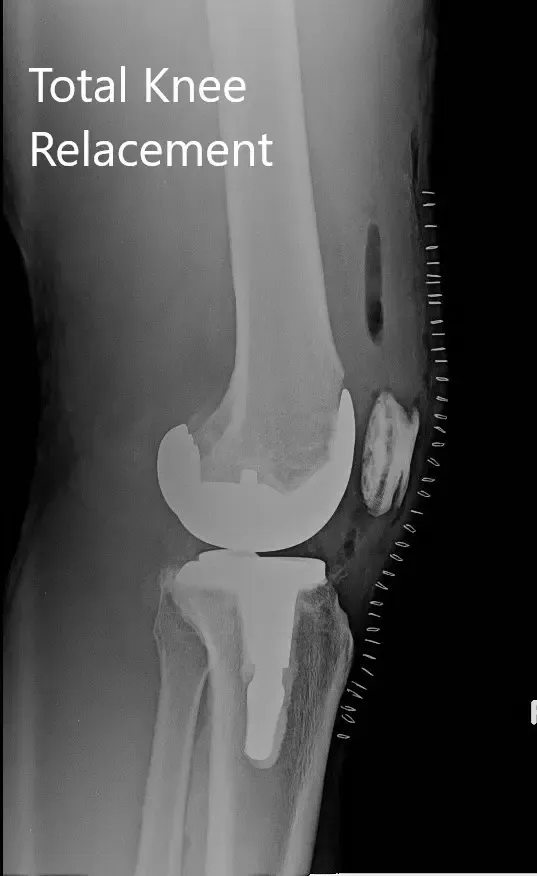

Radiografía postoperatoria de la rodilla derecha con prótesis en vistas anteroposterior y lateral.

IMPLANTES UTILIZADOS: Fémur estabilizado posterior, tamaño 11, tibia tamaño F, tallo afilado y polietileno estabilizado posterior restringido de 12 mm.